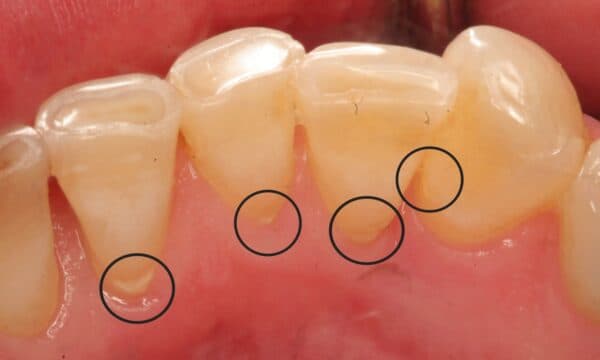

Vôi răng là những mảng bám cứng đầu, hình thành từ sự tích tụ của các khoáng chất trong nước bọt và các mảnh vụn thức ăn. Chúng thường bám chặt vào bề mặt răng, đặc biệt là ở những vị trí khó làm sạch như kẽ răng, viền nướu. Không cạo vôi răng định kỳ có thể dẫn đến những hậu quả nghiêm trọng sau:

– Sâu răng: Vôi răng tạo môi trường thuận lợi cho vi khuẩn gây sâu răng phát triển, đặc biệt là ở những vùng răng tiếp xúc với vôi răng.

Lượng vôi răng càng nhiều, càng dày, và càng bám chắc thì thời gian cạo sẽ lâu hơn và chi phí cũng sẽ cao hơn. Những trường hợp vôi răng nặng, bám sâu dưới nướu có thể đòi hỏi kỹ thuật cạo phức tạp hơn và cần đến các dụng cụ chuyên biệt.